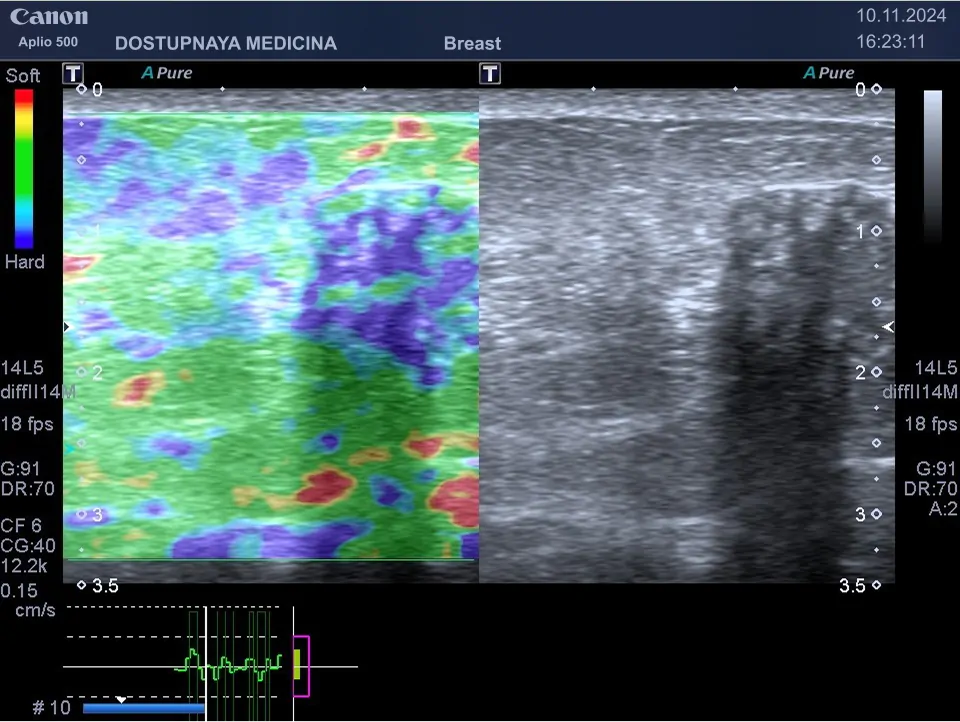

Клинический пример №1: опухоль у той же пациентки, при проведении компрессионной эластографии образования молочной железы, выполненной на УЗ-аппарате CANON (TOSHIBA) APLIO-500, картирование образования однородное, синего цвета, соответствует 4-му типу — по шкале Ueno, незначительно больше по размерам с серошкальным изображением. Эластографическая картина образования соответствует категории BI-RADS V, установленной при выполнении УЗИ в В-режиме.